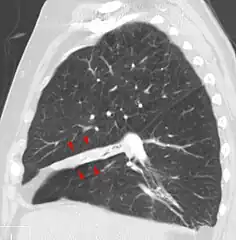

Clinically significant atelectasis is generally visible on chest X-ray; findings can include lung opacification and/or loss of lung volume. Post-surgical atelectasis will be bibasal in pattern. Chest CT or bronchoscopy may be necessary if the cause of atelectasis is not clinically apparent. Direct signs of atelectasis include displacement of interlobar fissures and mobile structures within the thorax, overinflation of the unaffected ipsilateral lobe or contralateral lung, and opacification of the collapsed lobe. In addition to clinically significant findings on chest X-rays, patients may present with indirect signs and symptoms such as elevation of the diaphragm, shifting of the trachea, heart and mediastinum; displacement of the hilus and shifting granulomas.[10]

- a) Subsegmental atelectasis b) atelectasis had rapidly progressed the following day

- Atelectasis of the middle lobe on a sagittal CT reconstruction.